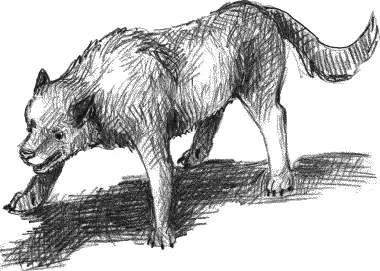

Батарею методик составили: наблюдение, беседа, пиктограмма, предметная классификация, запоминание 10 слов, проективные рисуночные методики (см. рис. 8–10), опросник личностной тревожности в адаптации А.М. Прихожан, незаконченные предложения.

а)

б)

Рис. 10. «Два настроения: а) хорошее и б) плохое»